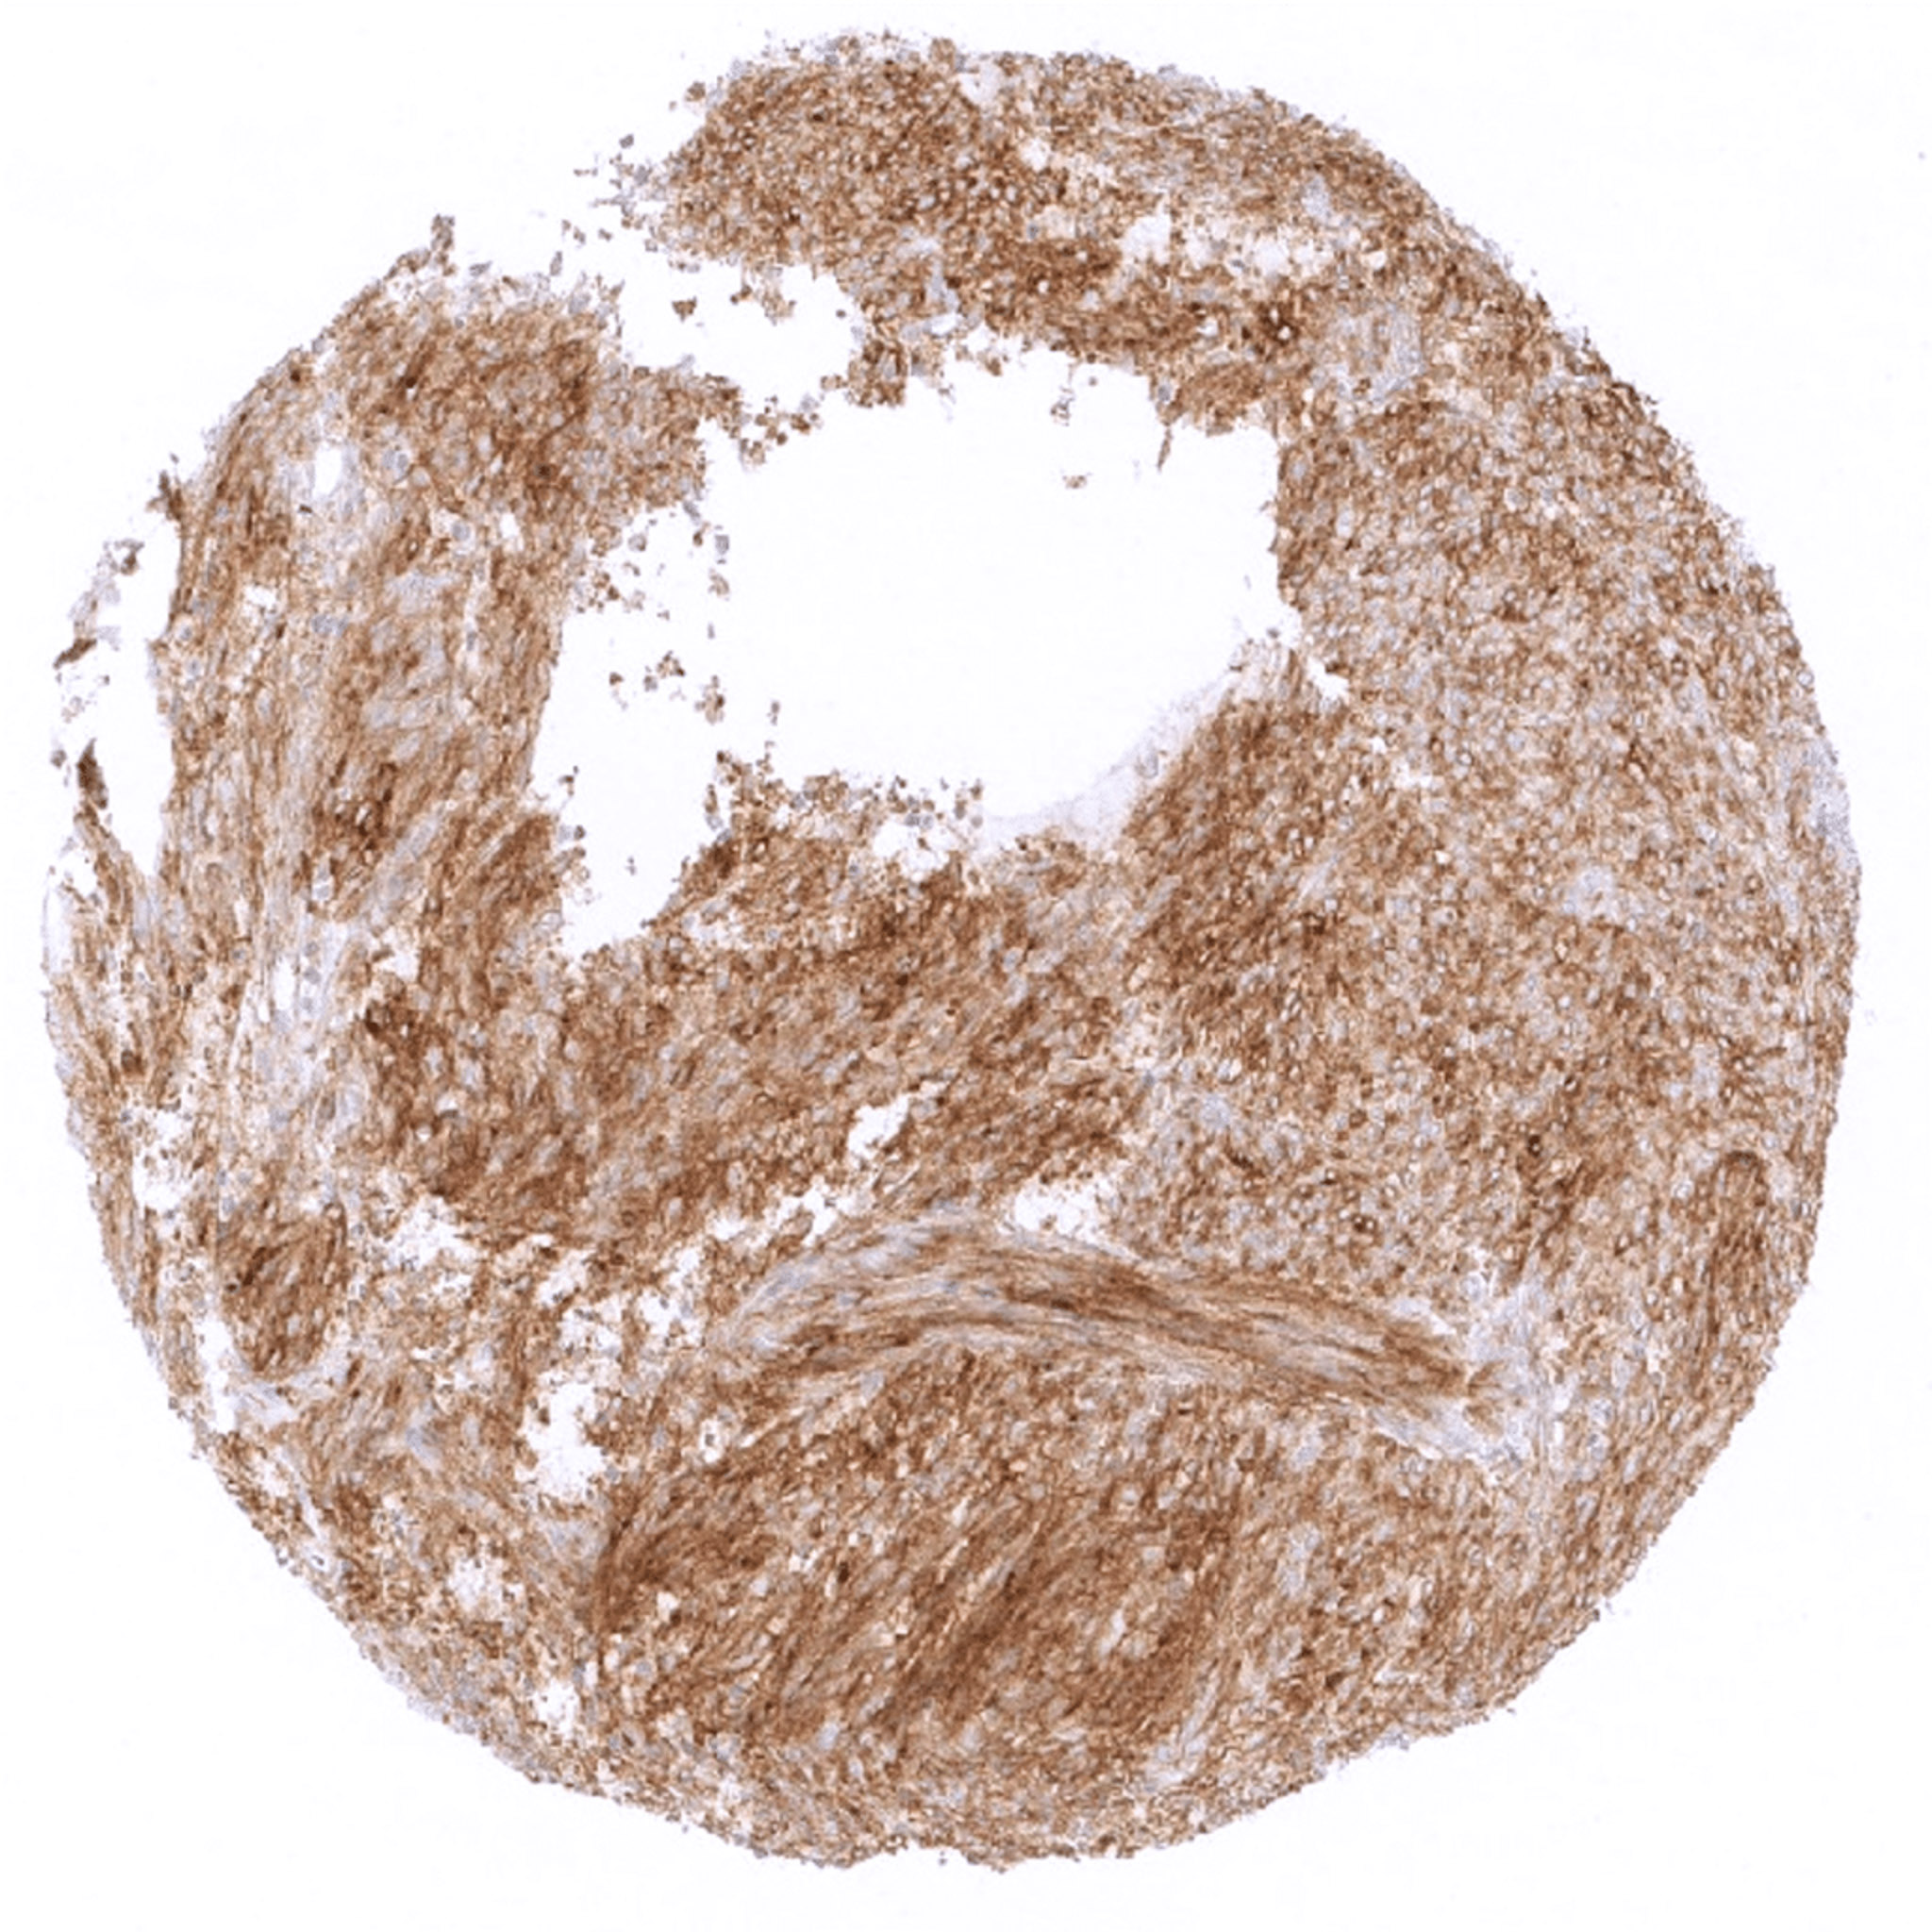

Stomach – Strong PD-L1 positivity in all tumor cells of a gastrointestinal stromal tumor (GIST).